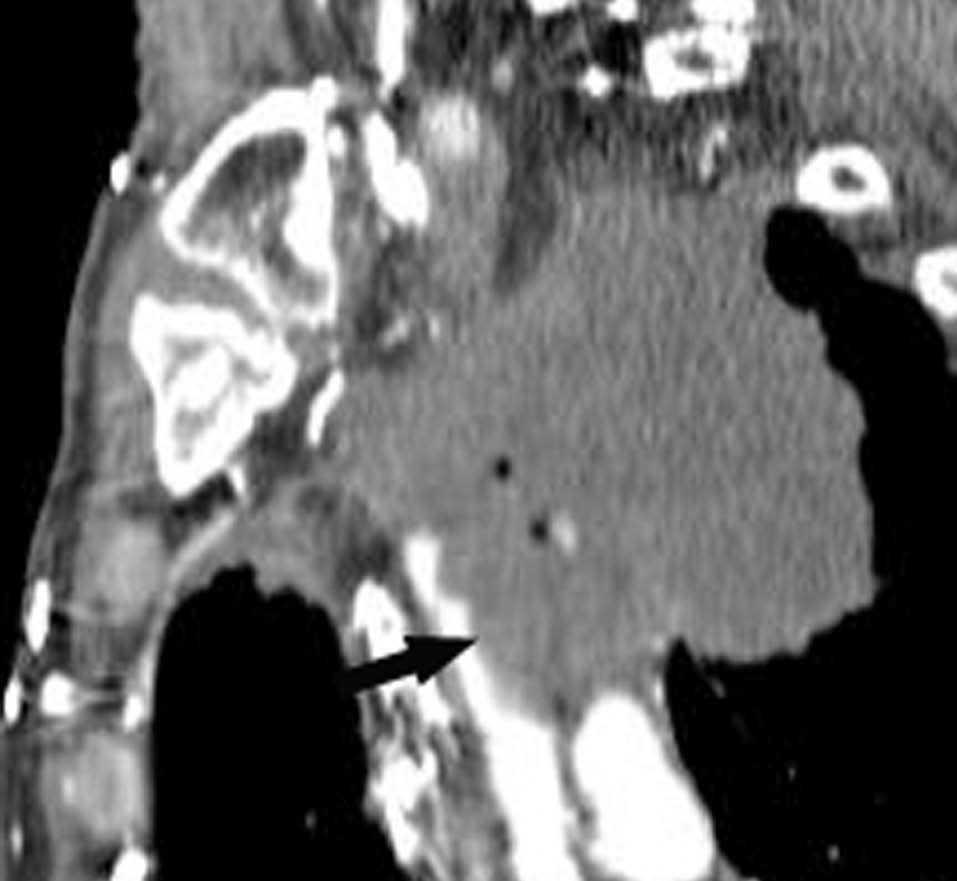

La resonancia magnética (RM) se utiliza principalmente para solventar problemas puntuales, y cada vez se emplea menos dado que la TCMD se ha equiparado con la RM en la capacidad de reconstruir en cualquier plano del espacio. Actualmente, la RM se debe reservar para la evaluación de los tumores del sulcus superior, aunque hay autores que consideran que debe emplearse sólo cuando existe invasión del canal medular, ya que en el resto de las situaciones la TCMD da suficiente información para obviar dicha técnica10 (fig. 10).

Fig. 10.--Tumor del sulcus superior. Tomografía computarizada (TC). (A) TC torácica con contraste, con reconstrucción coronal. Masa cavitada que ocupa todo el segmento apical del lóbulo superior derecho y engloba la arteria lobar superior. (B) En la reconstrucción sagital, se pone de manifiesto la infiltración de la vena cava superior (flecha).